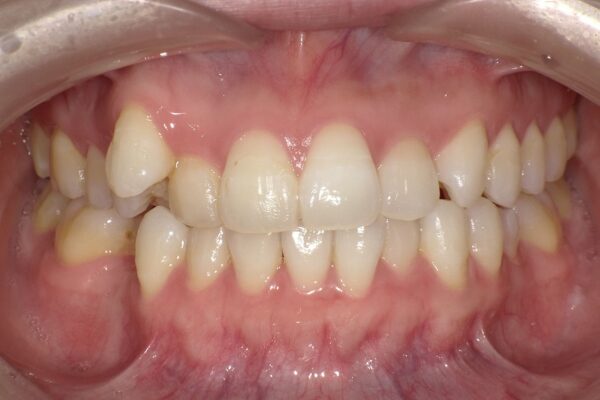

歯並びやお口のお悩み、

何でもご相談ください